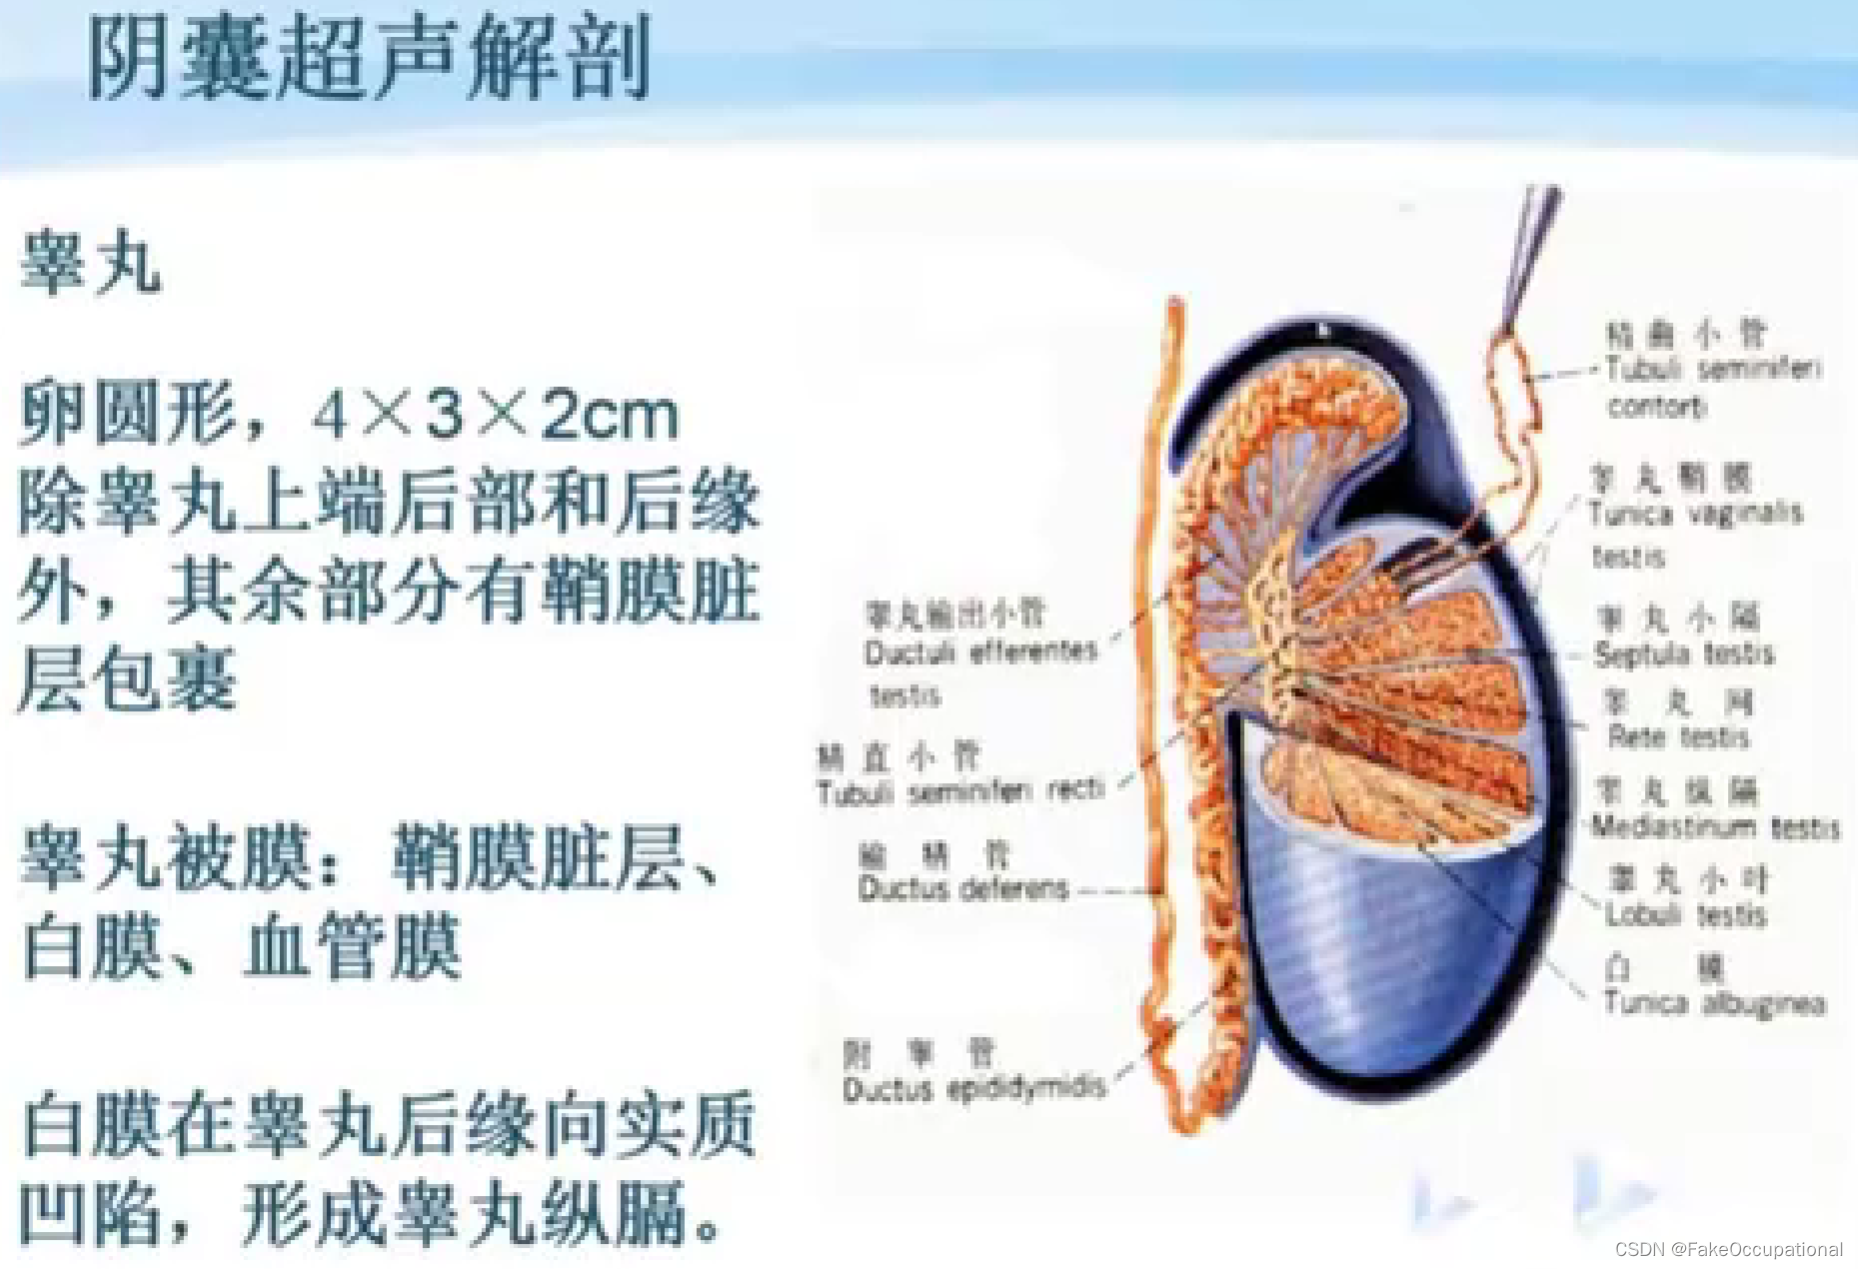

阴囊超声(和谐)